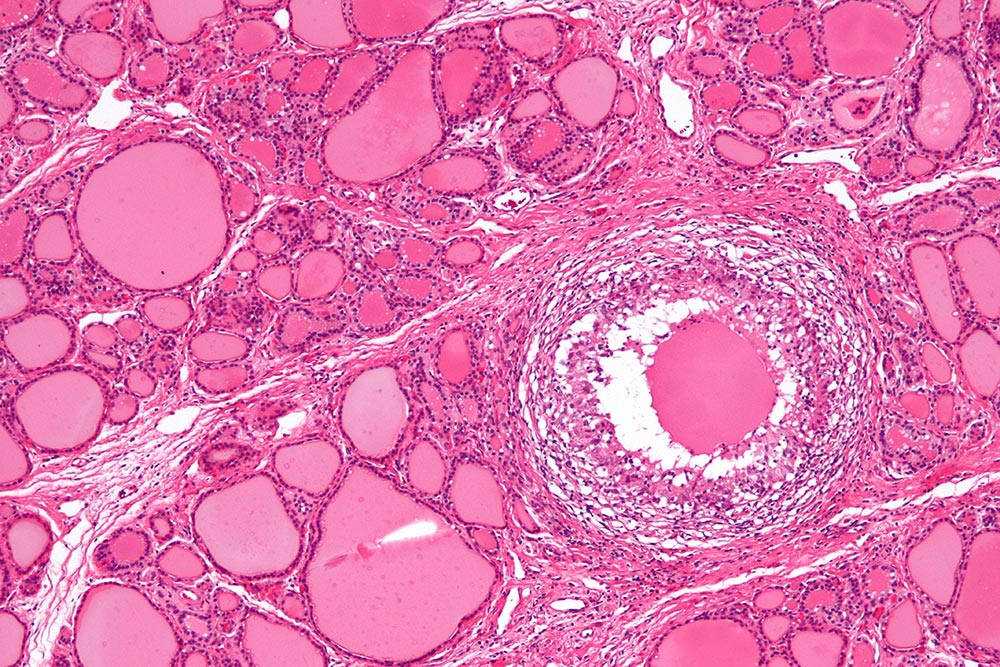

Slika: izgled subakutnega tiroiditisa pod mikroskopom.

Navadno poteka v dveh fazah, in sicer je v začetni fazi ščitnica povečana, trda ter boleča na dotik, bolečina se lahko širi v spodnjo čeljust, zatilje ali v uho, prisotna je bolečina ob požiranju, bolečine v sklepih in mišicah ter rahlo povišana telesna temperatura, v kolikor pa so vrednosti ščitničnih hormonov povišane, lahko bolnik tudi hujša, tresejo se mu roke, se močneje poti in čuti razbijanje srca. V fazi okrevanja pride do prehodne hipotiroze s simptomi kot so npr. utrujenost, zaspanost, dvig telesne teže, zaprtje ter depresija.